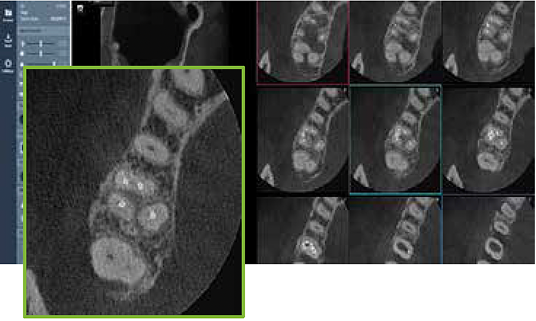

Game-changing Dentium MAR (Metal Artifact Reduction) with live comparison automatically reduces metal artifacts caused by implants, fillings or restoration. This helps to confirm diagnosis and reduces the risk of misinterpretation.

Endo mode provides with a maximum resolution of 80μm. Invert (Positive/ Negative) diagnostic mode helps identify more accurate images.lar nerve canal within 15 seconds. Dentium Al provides more accurate and reliable diagnosis.